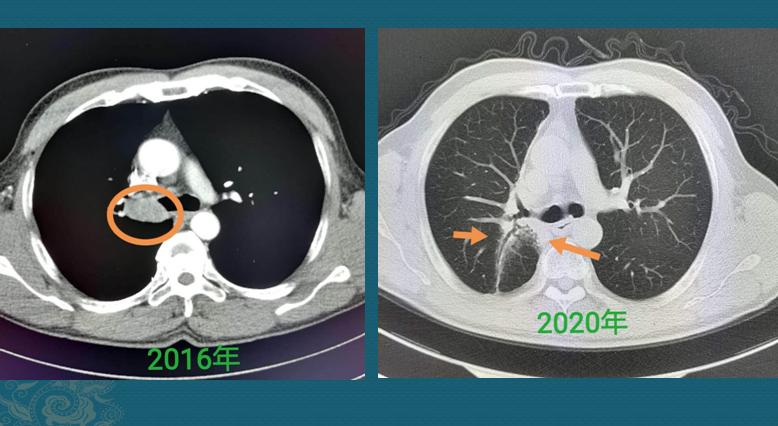

有些肿瘤属于惰性病灶(这种比较少见),癌细胞在较长一段时期内呈惰性进展,像动物冬眠一样,甚至十几年保持接近静止的状态。比如下面这个肺腺癌病例:

这位中年女士,体检发现左侧肺腺癌,表现为混合 磨 玻璃结节,形态不规则,伴有胸膜牵拉,肺门侧可见一支供血血管。她对手术非常恐惧,选择密切观察,很幸运,她的这个病灶非常懒,一直到11年后才发现增大迹象,表现为密度增加,实在不敢再拖了,最终手术切除,治愈!